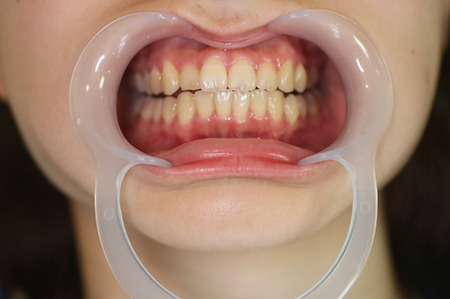

8あごの痛み/歯ぎしり【根の治療】

治療前